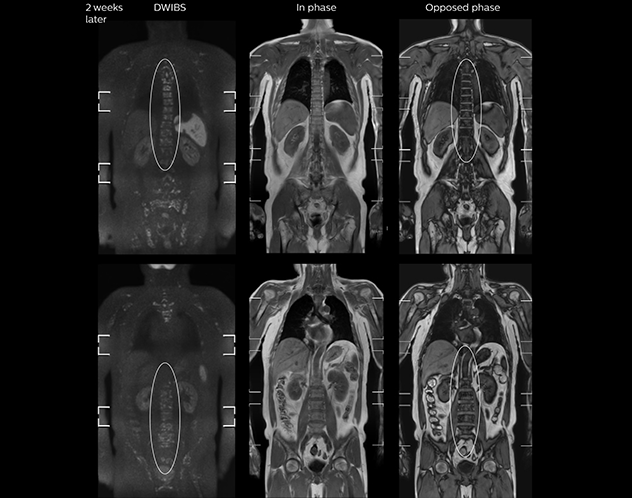

Kawasaki Sawai Hospital’s whole body protocol also includes an mDIXON FFE sequence. Because mDIXON provides images for four contrast types – water only, fat only, in-phase and out-of-phase – from a single acquisition, it is useful in many ways.

“mDIXON FFE allows us to quickly get information we need to assess the presence of fat. That gives us more information when we need to diagnose bone lesions, and when we are asked to judge fat-containing lesions such as hepatocellular or renal carcinoma,” Dr. Nobusawa says.

“The mDIXON fat images can help us to differentiate fatty bone marrow from bone lesions. This is especially useful in elderly people, who tend to have fattier bone marrow. The water images provide a high signal-to-noise ratio in the intestinal canal, which is valuable for visualizing lesions in the colon,” he says.

“In-phase and out-phase sagittal T1-weighted FFE images help us to visualize and further characterize bone lesions such as metastasis and bone-marrow hyperplasia that have high signal on DWI. These images are also used throughout radiotherapy, to monitor changes in the fatty bone marrow.”